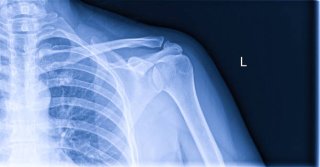

특징적으로 밤에 통증이 심하고, 자려고 누우면 어깨가 욱신거리거나 찌르는 듯 아픕니다. 엑스레이나 초음파 검사로 쉽게 확인할 수 있으며, 체외충격파나 주사치료로 비교적 잘 치료됩니다.

특히 날씨가 추워질 때 통증이 악화되며, 밤에 누워 있을 때 어깨가 욱신거리는 경우가 많습니다. 엑스레이 검사로 쉽게 확인 가능하며, 초기에는 운동치료와 약물치료로 관리하지만, 심하면 인공관절 수술이 필요할 수 있습니다.

- X-ray: 관절염, 뼈 손상, 석회성 병변 확인